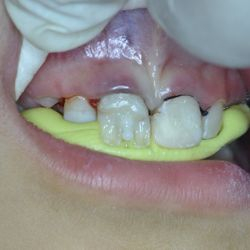

Το 9χρονο αυτό κοριτσάκι έσπασε τους κεντρικούς άνω τομείς μετά από πτώση στο έδαφος.

Τα δόντια απονευρώθηκαν και στη συνέχεια αποκαταστάθηκαν με συνδιασμό τοποθέτησης ενδοριζικών αξόνων και ανασυστάσεων σύνθετης ρητίνης.

Συγκεκριμένα, άξονες υαλονημάτων τελευταίας τεχνολογίας (ParaPost FiberWhite/Coltene και FiberCone/RTD) συγκολλήθηκαν εντός των ριζών και τα δόντια ανασυστήθηκαν με νανουβριδική σύνθετη ρητίνη (Herculite XVR Ultra/Kerr) με την βοήθεια ειδικής μήτρας/οδηγού από σιλικόνη.